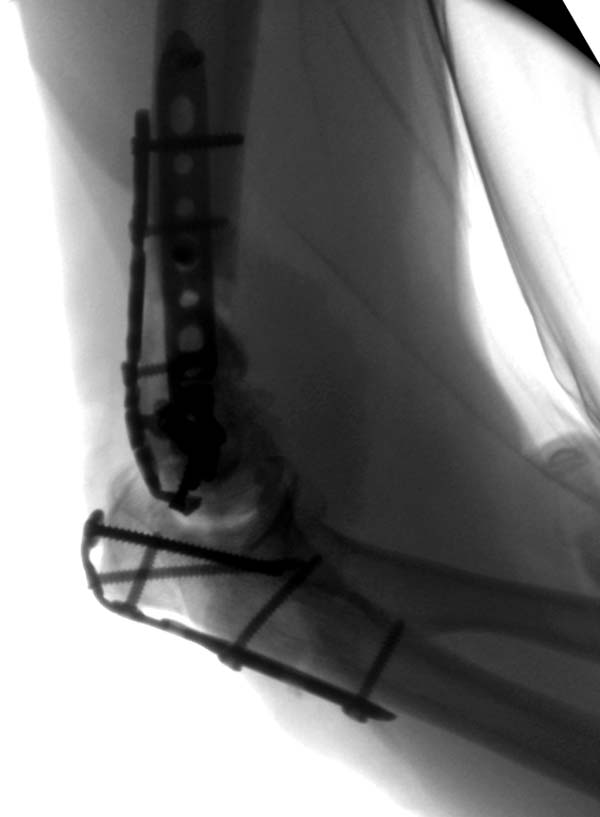

Технология не стоит на одном месте, и вместо спиц пришли менее раздражающие преконтурные пластины. Их можно уложить перед остеотомией, затем удаляют и сохраняют до конца операции вместе с шурупами. По окончании операции пластина укладывается на готовые дырки.

Разработаны различные концепции установки пластин на дистальное плечо: две параллельные в 180 или под углом в 90 градусов. Почти все компании имеют все варианты пластинок, а Acumed признает так называемую Keystone concept http://www.acumed.net/distal-humerus-plates

Для сохранения хряща пересмотрен вопрос линии остеотомии, вместе внутрисуставных делаются внесуставные.

Примеры: первому более 15 лет фиксирован шурупом и tension band technique, а второй перелом открытый больной 80 лет, после наружного фиксатора в первом этапе и окончательная фиксация вторично. Третьий раз внесуставная остеотомия...